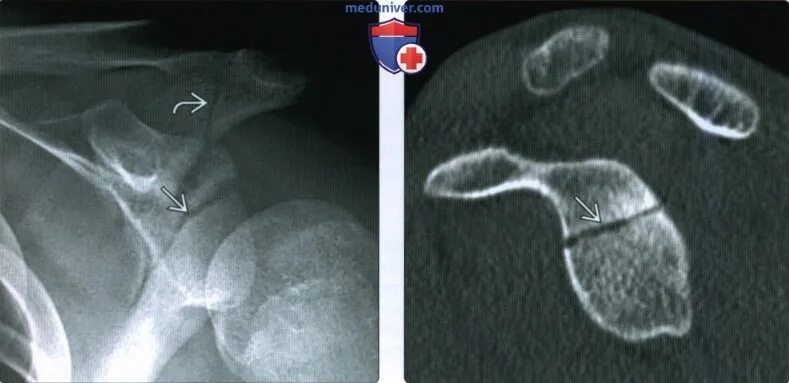

Перелом мрт или кт